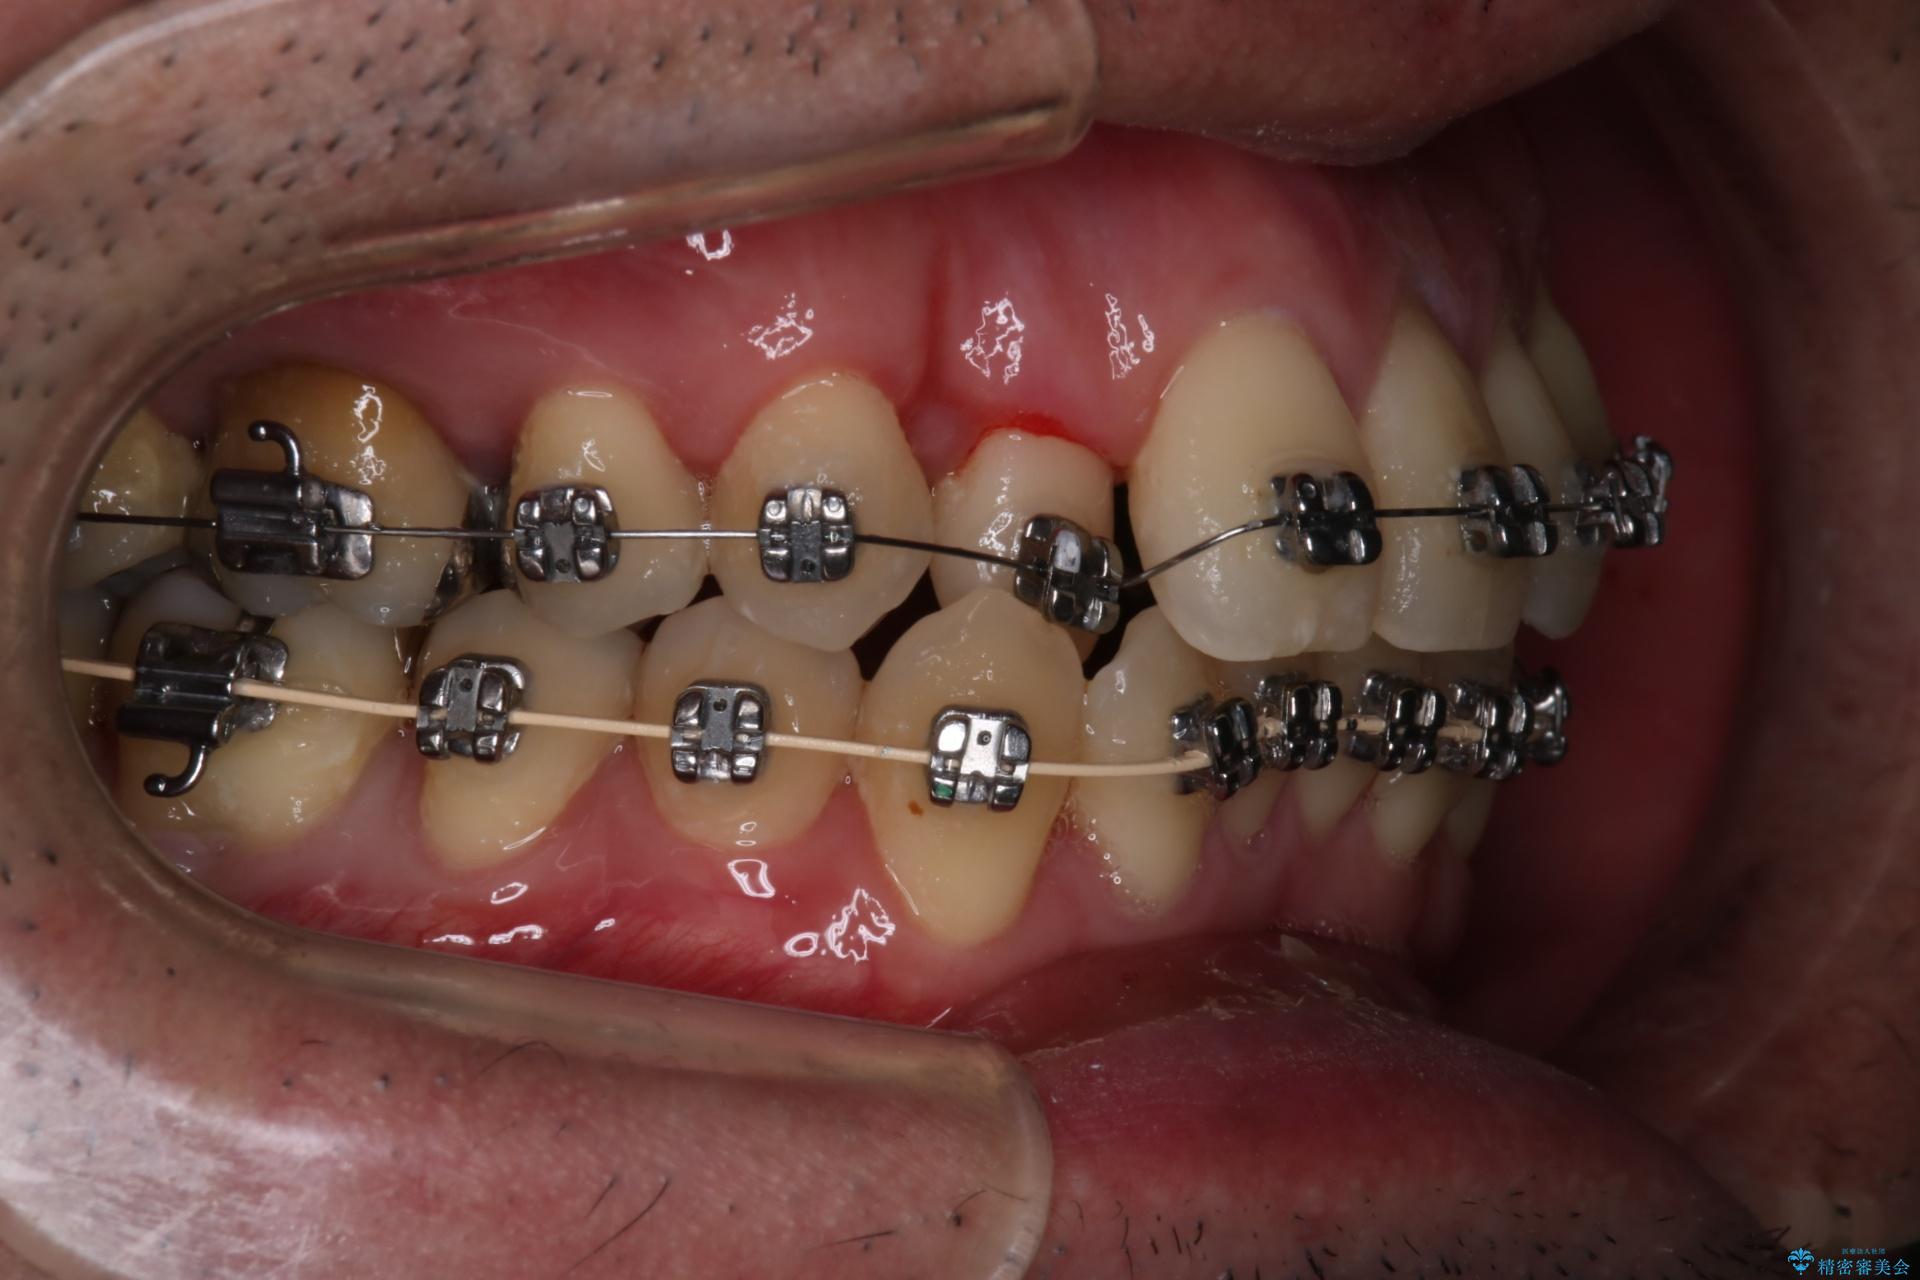

- 矯正装置

- メタル装置

- 治療期間

- 1年5ヶ月

右上の犬歯が初診時よりかなり歯根露出しており、矯正の力をかけるとさらに歯根露出するリスクがあるため、右上の2番目の歯を前に出すためにも

右上の犬歯を抜歯して歯並びを整える治療計画を立てました。

下のがたつきをとるために、IPR(歯と歯の間を削る処置)も行って歯を並べていきます。